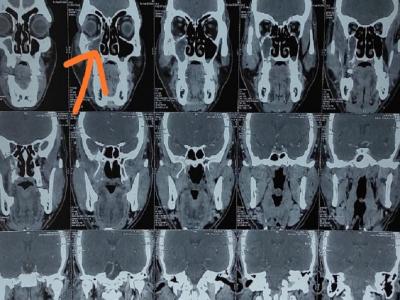

कोरोना संकट के बाद 'म्यूकोरमिकोसिस' के बढ़े मामले (प्रतीकात्मक तस्वीर)

ये फंफूदी हमारे ही वातावरण में होते हैं। इसका संक्रमण आम तौर पर नाक से शुरू होता है और आंखों तक फैल जाता है। इसका जल्द इलाज अगर शुरू किया जाता है तो बीमारी को ठीक किया जा सकता है। हालांकि, अगर लापरवाही हुई या इसे छोड़ दिया गया तो ये जानलेवा तक साबित हो सकता है।

'म्यूकोरमिकोसिस' बीमारी में जैसे-जैसे संक्रमण फैलता है, ये आंखों की पुतली के आसपास की मांसपेशियों को पैरालाइज कर देता है। इसे आगे जाकर अंधापन हो सकता है। अगर फंगल संक्रमण ब्रेन तक पहुंचा तो मरीज को मस्तिष्क ज्वर (Meningitis) भी हो सकते हैं।